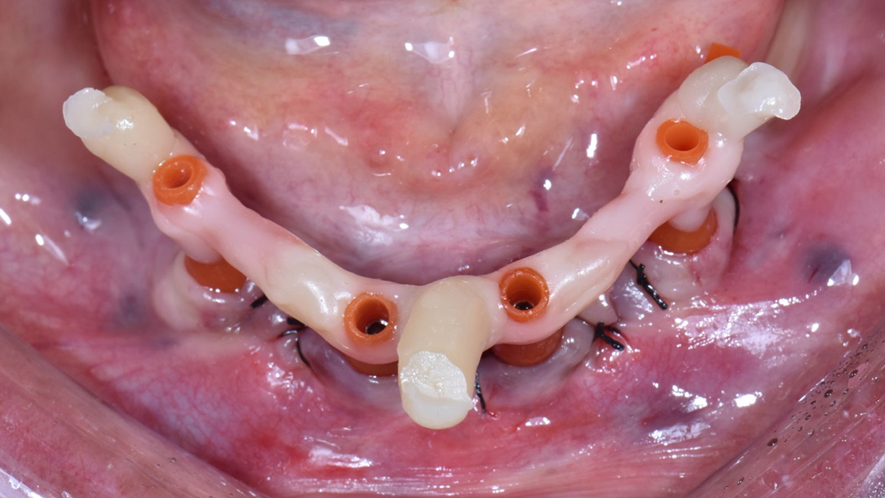

A utilização de scan bodies horizontais demonstra melhor veracidade e precisão quando comparamos com o escaneamento utilizando apenas os scan bodies convencionais. Para isso, eles devem ser conectados, porém não devem ficar unidos, permitindo que o formato do arco seja seguido durante a conexão dos scan bodies.

Neste caso clínico foi utilizado o novo corpo de escaneamento para arcos desdentados totais da Implacil Osstem. Os corpos de escaneamento são encaixados no scan body através de encaixes de precisão e são disponibilizados em três tamanhos diferentes (5, 10 e 15mm) para que eles possam ficam próximos entre si e facilitar a leitura pelos scanners intraorais.